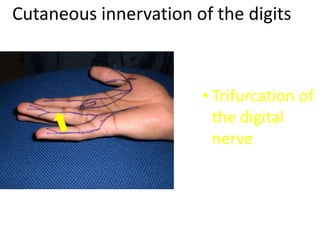

- Naming the bones, joints, tendons, nerves and skin landmarks of the hand and wrist.